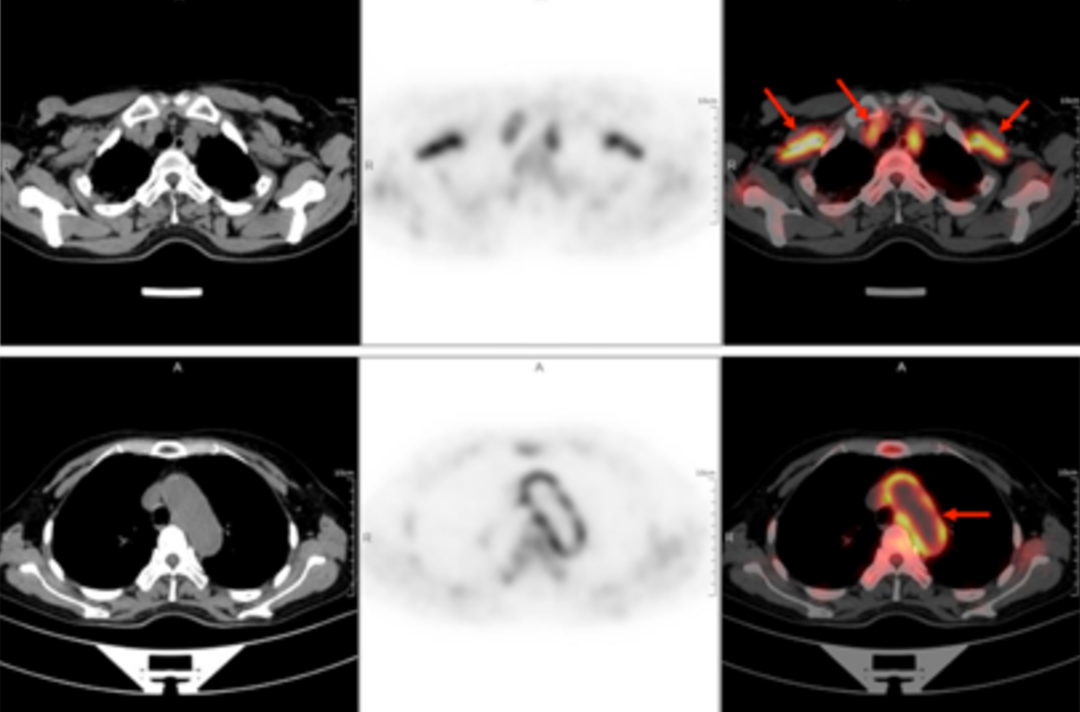

58-letnia kobieta trafiła do szpitala z powodu gorączki trwającej z przerwami od ponad 40 dni. Najwyższa zmierzona temperatura ciała wynosiła 38,9℃. Inne objawy obejmowały zmęczenie i ból stawów barkowych szczególnie nasilony po południu oraz nocą, dreszcze, krwioplucie, ból i ucisk w klatce piersiowej oraz duszności. Po dwóch tygodniach dożylnego podawania antybiotyków cefalosporynowych nie było poprawy, a gorączka się utrzymywała. W poradniach odnotowywano u pacjentki „gorączkę nieznanego pochodzenia”. W badaniu przedmiotowym nie znaleziono ewidentnych wskazówek pozwalających na diagnozę. Wyniki rutynowego badania krwi były następujące: wskaźnik sedymentacji erytrocytów w pierwszej godzinie – 72 mm; białko C-reaktywne o wysokiej czułości: 204,20 mg/l. Następnie u chorej wykonano badanie PET/TK całego ciała z zastosowaniem znacznika F-FDG (fluorodeoksyglukozy) w celu znalezienia przyczyny gorączki nieznanego pochodzenia.

W obrazach PET/TK w kilku lokalizacjach (obustronna tętnica szyjna wewnętrzna, tętnica szyjna wspólna, pień ramienno-głowowy, obustronne tętnice podobojczykowe i pachowe, aorta piersiowa, aorta brzuszna, obustronna tętnica biodrowa wspólna, tętnica biodrowa wewnętrzna, tętnica biodrowa zewnętrzna i tętnica udowa) wystąpiło pogrubienie ściany ze zwiększonym metabolizmem glukozy, co uznano za spowodowane zmianami zapalnymi. Na podstawie wywiadu lekarskiego, objawów klinicznych, badania i wyników badań obrazowych u pacjentki rozpoznano zespół Takayasu. Po zastosowaniu standardowego leczenia przeciwzapalnego temperatura ciała spadła, a stan pacjentki uległ poprawie.

Przedstawiony przypadek jest typowym przykładem zastosowania PET/TK ze znacznikiem F-FDG w diagnostyce zespołu Takayasu.

Badanie PET/TK z F-FDG może umożliwić zdiagnozowanie zespołu Takayasu i ocenić chorobę w jej fazie aktywnej. Ponadto skanowanie całego ciała może również pozwolić na określenie obszaru zmian chorobowych, stanowić podstawę do ustalenia lokalizacji biopsji tętnicy oraz zapewnić monitorowanie odpowiedzi organizmu pacjentki na leczenie. Może też umożliwić jakościowe rozpoznanie zwiększonego metabolizmu w miejscu dotkniętym chorobą. Półilościowy wskaźnik maksymalnego standardowego wychwytu SUVmax jest przydatniejszy od wskaźników surowicy krwi, takich jak ESR i CRP, w czułym i swoistym wykrywaniu zespołu Takayasu, co może zwiększyć dokładność diagnostyczną.